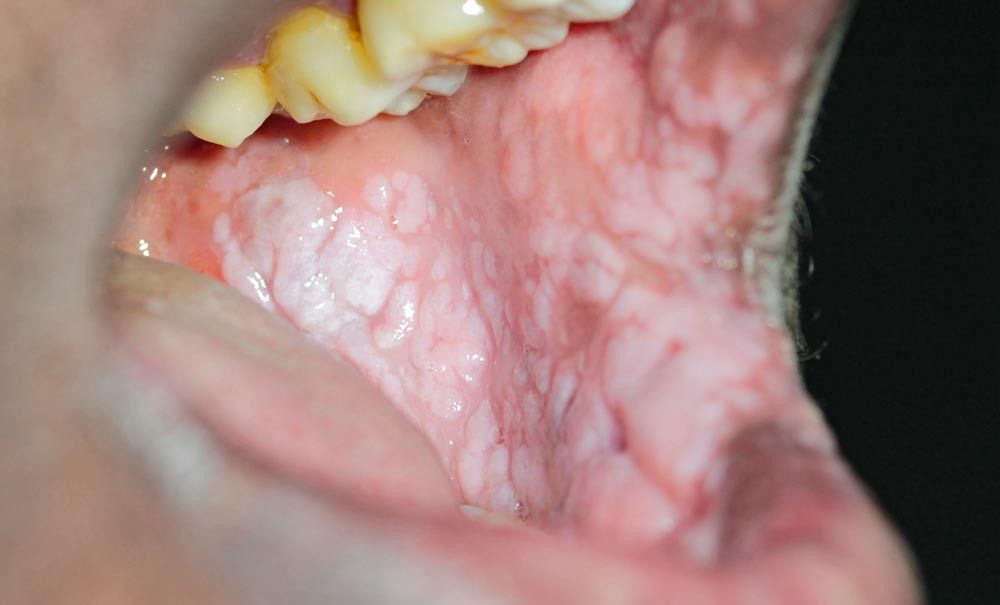

Le papillomavirus (HPV) est un virus à transmission interhumaine possédant de nombreux génotypes. Ses manifestations cliniques au niveau de la cavité orale peuvent se classer en deux catégories : les lésions bénignes (papillomes, condylomes et verrues) – dont le traitement relève majoritairement de la chirurgie – et les lésions malignes avec les carcinomes épidermoïdes HPV+ provoquées majoritairement par les génotypes 16, 18 et 31 – dont l’incidence est en hausse par rapport aux carcinomes épidermoïdes HPV. Depuis plusieurs années, une vaccination existe contre les génotypes les plus virulents, recommandée chez les adolescents à partir de 11 ans jusqu’à 19 ans. Cette vaccination permet une diminution du nombre de lésions HPV induites, mais reste minoritaire dans la population ciblée (en France au 31 décembre 2023, 44,7 % chez les jeunes filles et 15,8 % chez les garçons, âgés de 16 ans).

L’infection à papillomavirus est l’infection sexuellement transmissible (IST) la plus fréquente. À travers le monde, environ 5 à 10 % de la population est infecté par un Human Papilloma Virus (HPV) [1]. Le virus du papillome humain (HPV) est un virus à ADN double brin. Il en existe plus de 200 types, dont une douzaine peut provoquer des cancers du col de l’utérus, de la vulve ou de l’oropharynx [2]. En 2019, l’HPV a été responsable d’environ 620 000 cas de cancers chez les femmes et 70 000 cas de cancers chez les hommes.